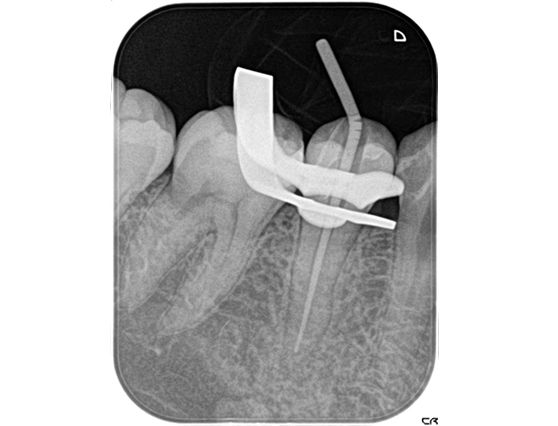

根管治療 症例9

| 治療中 | ![]() |